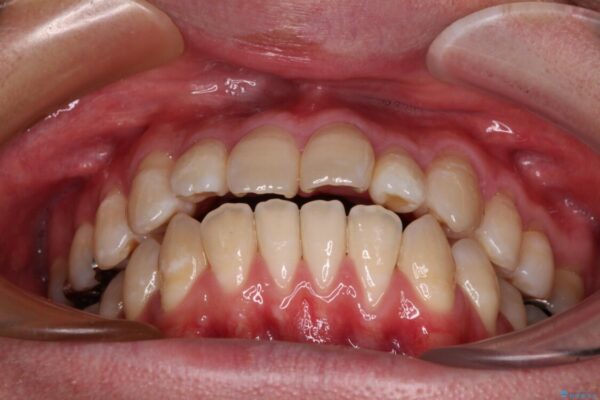

治療後

• 口元の突出感を改善!目立ちにくいワイヤー矯正で自信を持てる自然な横顔に 治療後画像

少しずつ前歯を後ろに下げていくことで、横顔のラインが整い、口元の“出っ張り感”が解消。

治療後には「自然に笑えるようになった」と嬉しいお声をいただきました。